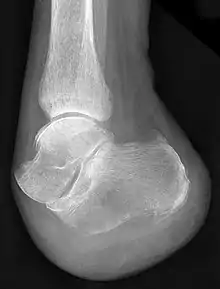

X-ray of a foot after "Chopart's amputation"